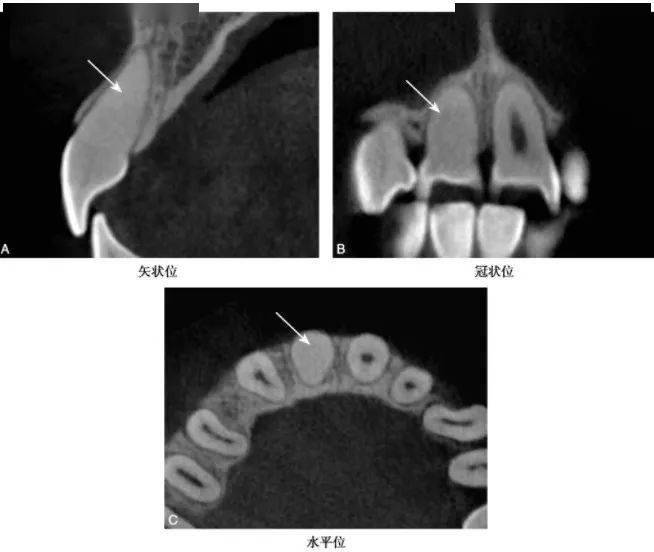

图2-2-5 A1弥散性钙化

CBCT示A1髓室、根管正常影像消失,呈均匀近牙本质密度影(白色箭头)